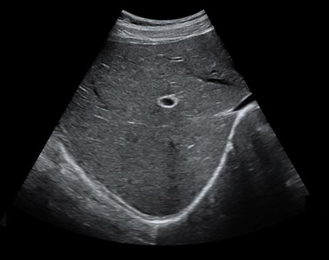

适用于腹部,妇产,泌尿等

腹部,胎儿检查